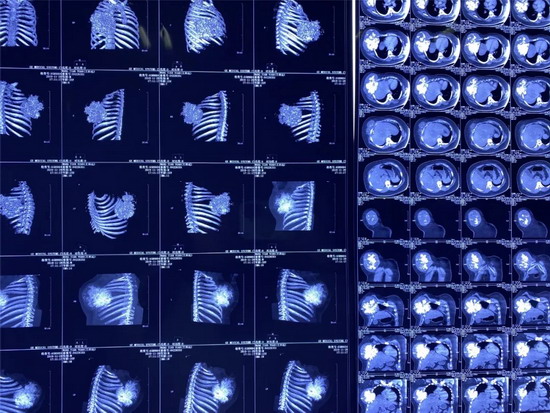

经专家的推荐,家人带着王某来到唐都医院胸腔外科就诊,CT检查显示右前胸壁肿瘤45×35厘米,穿刺活检结果为肋软骨源性恶性肿瘤。由于患者的软骨肉瘤恶性程度高,对放、化疗都不敏感,且易复发,手术切除是首选方案。此外,考虑到患者要切除五根肋骨,术后右前胸壁缺损大,医生决定采用3D打印技术,为王某进行胸廓重建。

2019年10月,王某来到了江苏省东台市某医院做了胸部CT检查。检查结果显示:王某右侧胸壁长了一个外径约45cmX36cm的巨型肿瘤,其右前肋骨骨质已经遭到破坏,医生考虑是软骨肉瘤。

两年前,王某突然右侧前胸长了大约3.0cmX2.8cm的包块,一年来包块逐渐增大还伴有隐痛不适,于今年10月就诊于江苏省某医院,经胸部CT检查示为右侧胸壁巨大肿瘤且右前肋骨骨质破坏,当地医生怀疑为软骨肉瘤,因无法治疗建议去北京诊疗,后经中国医学科学院肿瘤医院的专家推荐其来到唐都医院胸外科就诊。

2019年10月,王某来到了江苏省东台市人民医院,做了胸部CT检查。检查结果显示:王某右侧胸壁长了一个外径约45cmX36cm的巨型肿瘤,其右前肋骨骨质已经遭到破坏,医生考虑是软骨肉瘤。

2019年12月9日,小田来到唐都医院就诊,主管医生杨三虎为小田做了CT检查,显示右前胸壁巨大肿瘤,大小是45cm×35cm,鸡蛋大小的包块已经长成篮球大小的肿瘤,穿刺活检诊断为肋软骨源性恶性肿瘤。